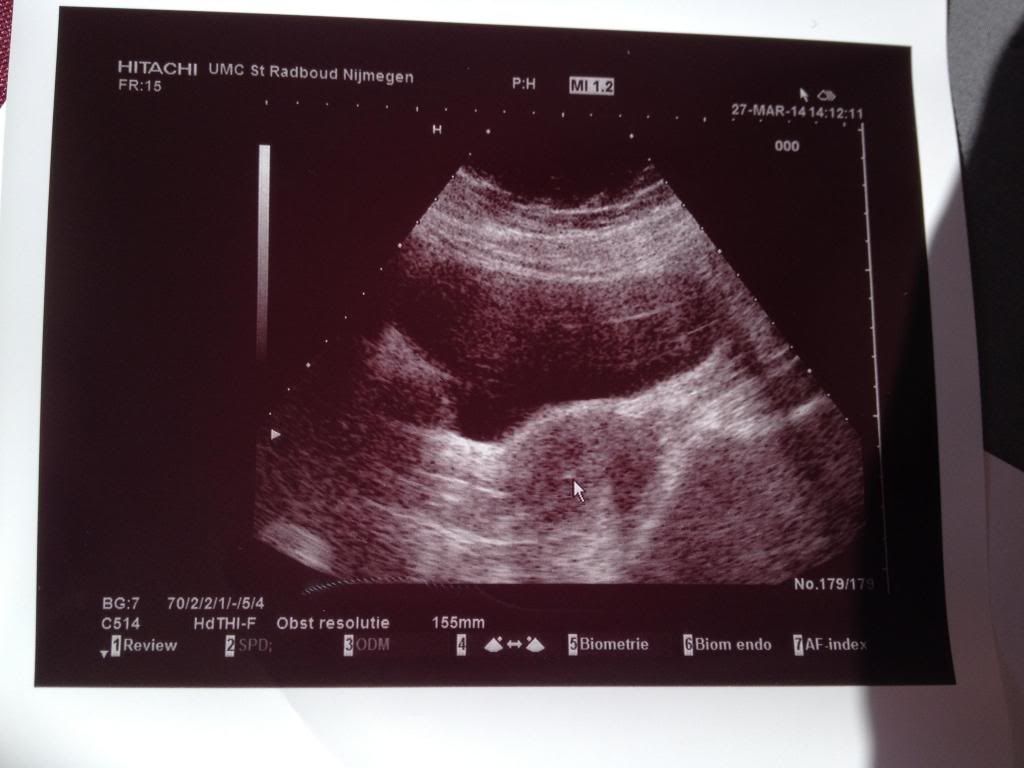

Toen we daar aankwamen waren we 20 minuten te vroeg. Maar ja, beter te vroeg als te laat. We mochten even wachten in de wachtkamer. Toen we precies om 14:00 werden gehaald, toen vroeg ze of ik een volle blaas had. Ja, ik durfde al vanaf 11:00 niet meer te plassen, dus ik had een behoorlijke volle blaas. We kregen meteen de foto van ons embryootje te zien. Wat een schatje, hè? Ik ben nu al dol op m'n kind. Hihi.

Helaas liep de rest niet zo goed. Net zoals de vorige keer konden ze mijn baarmoedermond niet vinden. Met de echo ging het wel goed, ik zag mooi mijn baarmoeder. Ze probeerde en probeerde, maar ze kon mijn baarmoedermond echt niet vinden. Gelukkig bleef ons embryootje lekker warm in de stoof, want dat was de vorige keer niet. Toen werd het veel te vroeg opgehaald en toen weer teruggebracht. Maar nu niet, nu bleeft ons embryootje veilig en warm in de stoof tot ze met mij klaar zouden zijn. Maar dat ging dus niet zo soepel. Ze probeerde op een gegeven moment een andere eendenbek en toen begon het pijn te doen. Ik wilde niet aan te stellen, dus ik zei niks, maar het deed echt pijn. Ik kneep mijn ogen dicht en probeerde me te concentreren. Helaas lukte dit ook niet en toen hebben ze iemand anders gebeld (een ervarener persoon). Zij is van vooraf aan begonnen en... het lukte! Niet meteen, maar toch vrij vlot! Toen werd de laborant erbij geroepen die ons embryootje meebracht. Ze stonden dus op een gegeven moment met z'n vijven om me heen! Dat was wel druk en voelt ook een beetje apart om zoveel kijkers naar je prive delen te zien turen. Ik keek maar op het schermpje. Ik kon meekijken op de echo en ik zag ons embryootje in mijn baarmoeder komen! (Zie witte stip bij pijl) We hebben een mooie echo-foto gekregen. Het is heel fijn om zo'n foto te hebben en ik koester de foto's echt.